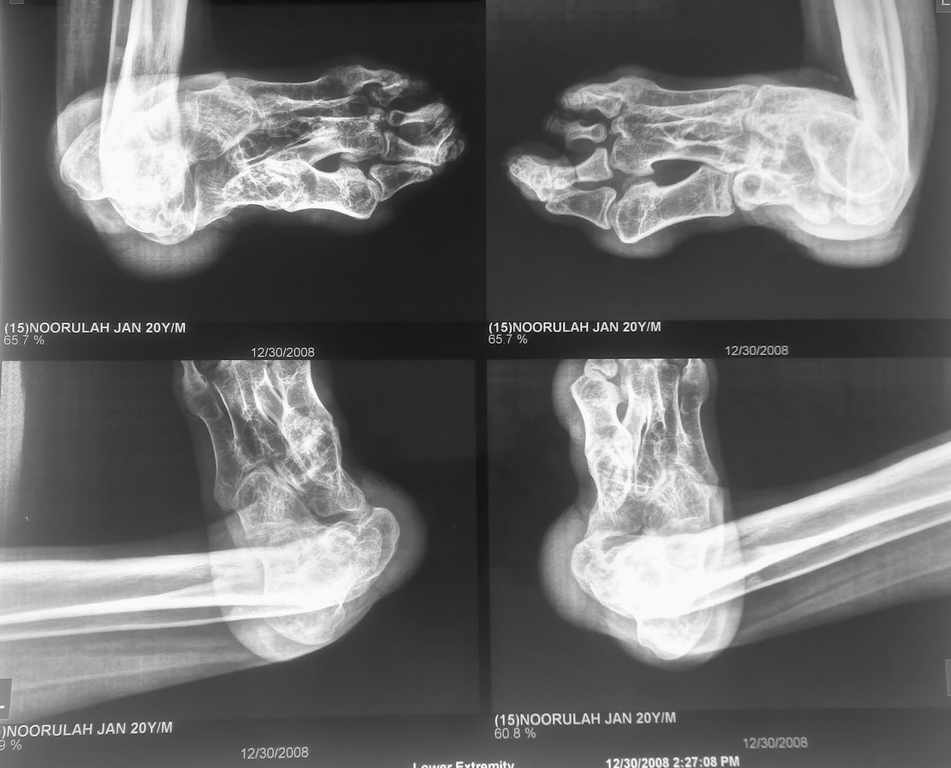

i have a patient 17 years of age, with post traumatic ankle joint dislocation,

he has walked with dislocation for 6 years now and has this deformity,, can some body suggest what would be the appropriate name to describe it, and treatment options

Looks like neglected subtalar foot dislocation. AP view of the ankle will help.

According to clinical picture and x-rays, I think that your patient has next problems- severe calcaneo-valgus deformity of the foot,

shortening of his leg, subtalar or ankle dislocation(?) and severe deformity of the distal end of tibia and fibula. In such case the reasonable solution will be - pantalar arthrodesis and lengthening of the leg.